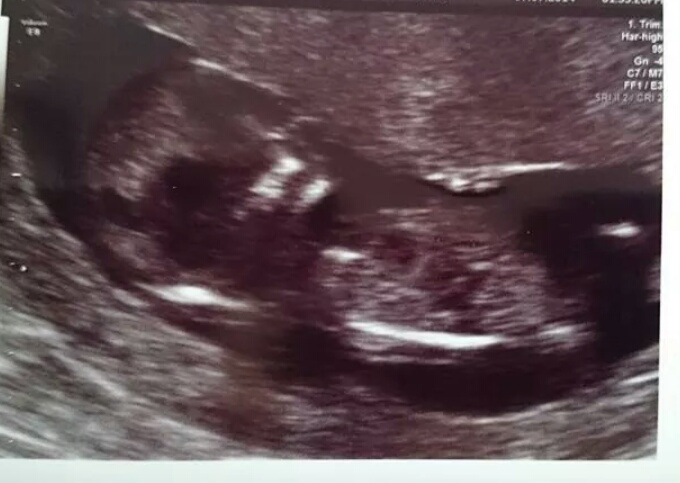

Hi all. I would be grateful if anyone would have a guess at gender based on this pic from my 12 week scan. Will hopefully find out at my 20 week scan, so only 18 days to wait :) Attachment 20297

Really. Tbh the pictures aren't nearly as clear as we had hoped as you could really see the nub on the screen. There is this one too...

Ok there's the nub :) girl!

*UPDATE * Booked a last minute gender scan and it is a boy